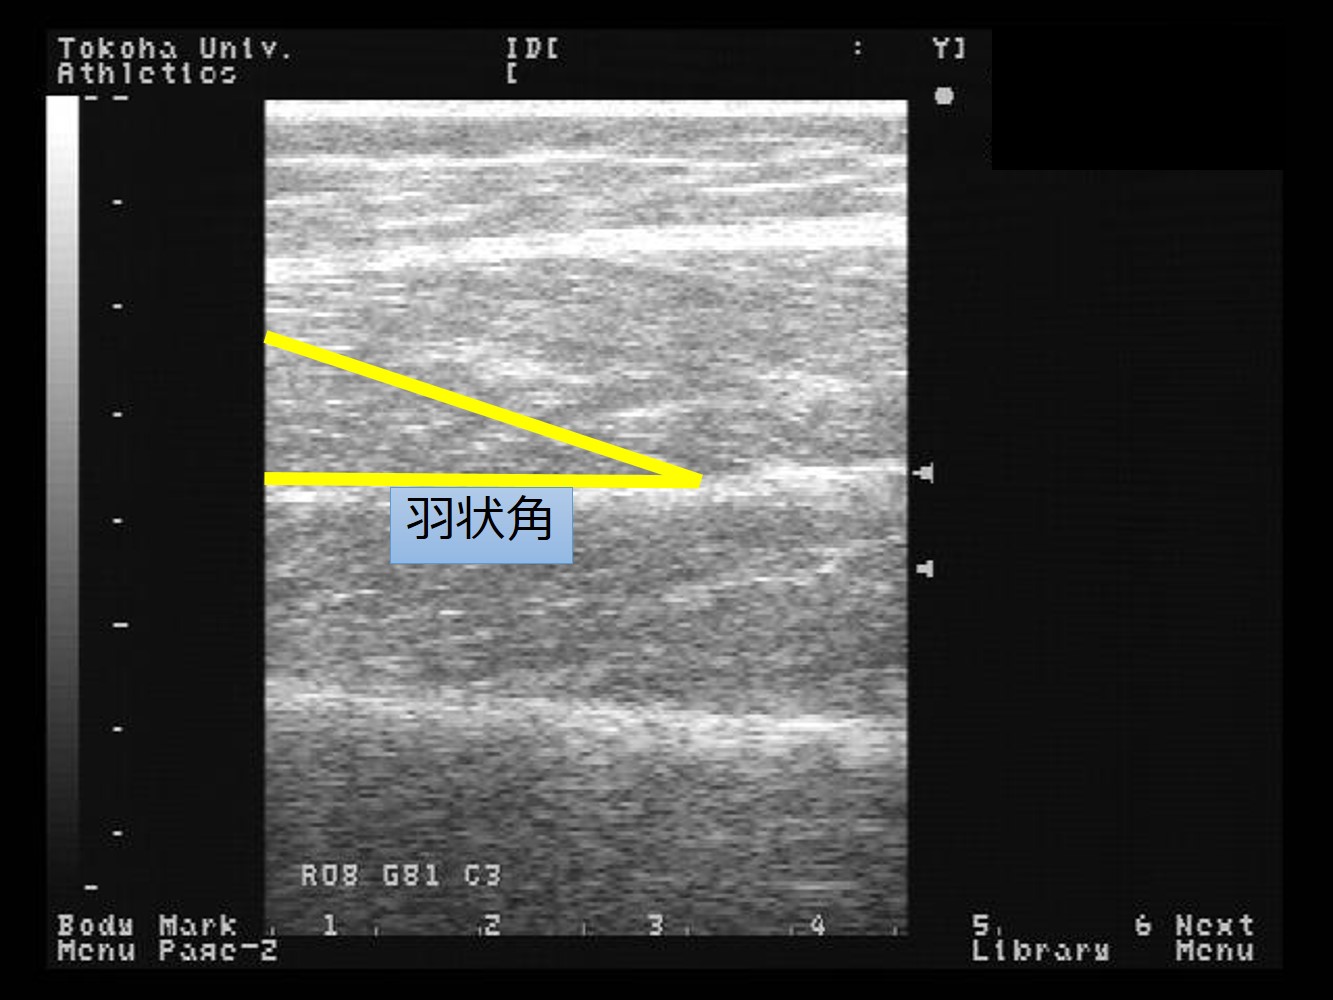

「形は力を産み、力は形を造る」という考え方から、アスリートに必要な骨格筋・腱複合体の形態や量と動作の関係について研究を行っています(骨格筋の筋厚、筋線維の羽状角、骨格筋の硬さ、動作分析[図1~4])。

図2